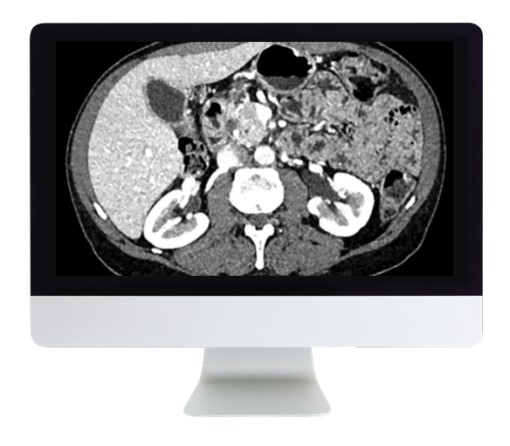

- -Discuss the imaging appearances of cystic pancreatic lesions and pancreatic neuroendocrine tumors

- Pancreatic Neuroendocrine Tumors—E. Tamm

- Cystic Pancreatic Lesions—E. Paulson

- Pancreatic Adenocarcinoma: Everything You Need to Know—B. Patel